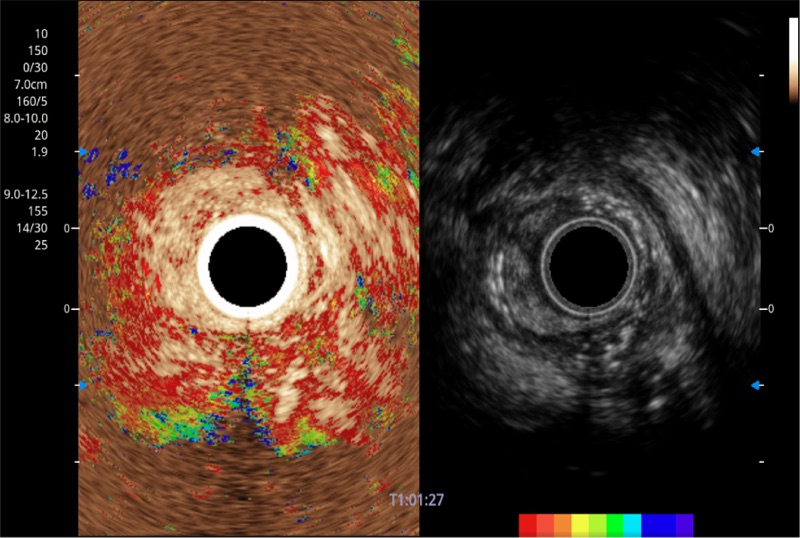

可人为将灰阶图像转变成彩色的显示方式,增强人眼对于不同回声强度的敏感度,主观上增加了图像分辨率

微米成像技术提升了对组织斑点噪声信号的抑制能力,并进一步强化边界信息,从而获得信噪比更优、边界更清楚锐利的图像

随着组织深度的变化,超声接收频率进行智能匹配跟踪,确保图像中、远场良好的穿透力以及整场一致的分辨力,从而得到均一的画质